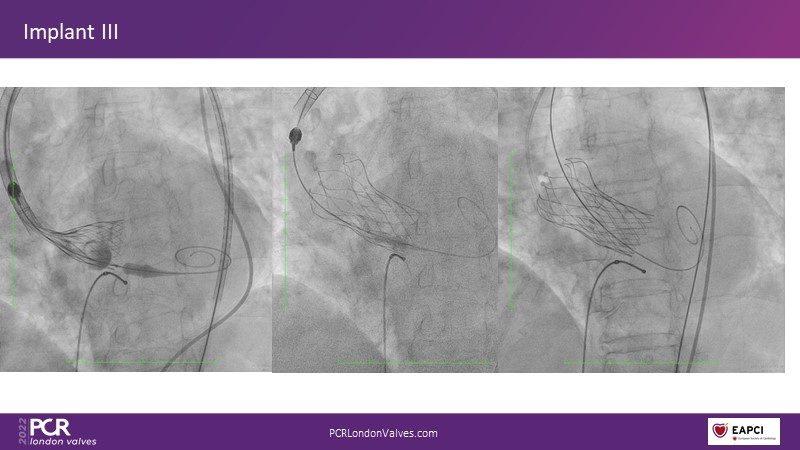

In this session, a panel of experts introduce the VitaFlow TAVI system, a good option for patients with complex anatomies. They also present the five-year results of VitaFlow in severe aortic stenosis.

- To discuss the use of VitaFlow in bicuspid aortic valve stenosis

- To understand the outcomes of VitaFlow Liberty in pure aortic regurgitation